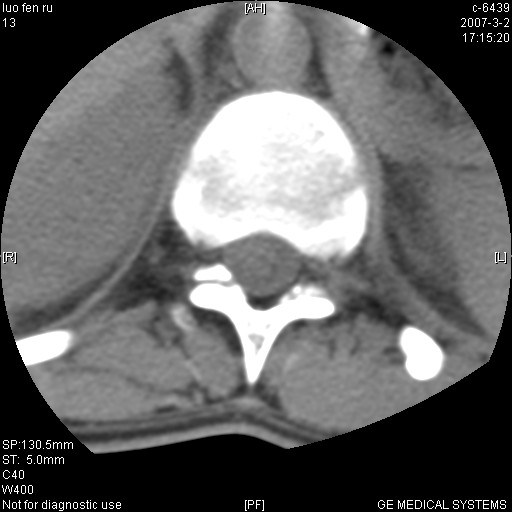

t11椎体前缘不规则形骨质破坏,周围有硬化边,软组织肿块不明显,首先考虑:骨嗜酸性肉芽肿 。期待随访结果。

病人病史不长,病变表现比较明显,如果是结核,病史不支持,椎间隙不窄,临近椎体正常,椎旁无冷浓疡,但从病变本身硬化也较多,均不太支持结核。慎重考虑的话,可以问一下病人有无结核病史。如果没有,更多的应该考虑陈旧性骨折,伴有慢性椎间盘炎可能。确诊后记着告知啊!

当是应是椎体(前半部较厉害)压缩性骨折,这就印证了这就是陈旧性骨折。